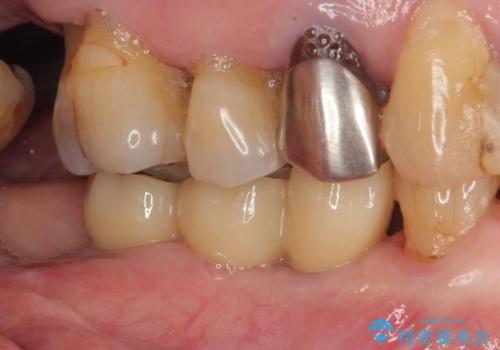

仮歯を速やかに撤去して力が一切かからない状態とし、1か月後と2か月後にそれぞれ安定値を測定することしました。

2か月後には無事に値が回復したため、セラミッククラウンにて補綴治療を行いました。